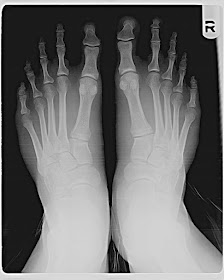

Esta particularidad lleva un nombre: si tienes un pie así, entonces tienes lo que se llama un “pie griego”. El pie griego generalmente es asociado con la fuerza, la inteligencia y el atractivo sexual. Y aunque esto sea bueno, también hay ciertas consideraciones que deberías tener en cuenta.

Para muchos es sólo una diferencia visual, sin embargo puede traer problemas a los pies y causar dolor si no se utiliza el calzado adecuado.

Al caminar o correr, los pies soportan la mayoría del peso del cuerpo. Esto no es algo menor. Las personas con “pies griegos” pueden sufrir dolores en esa zona e inflamaciones a las que hay que prestarles atención.